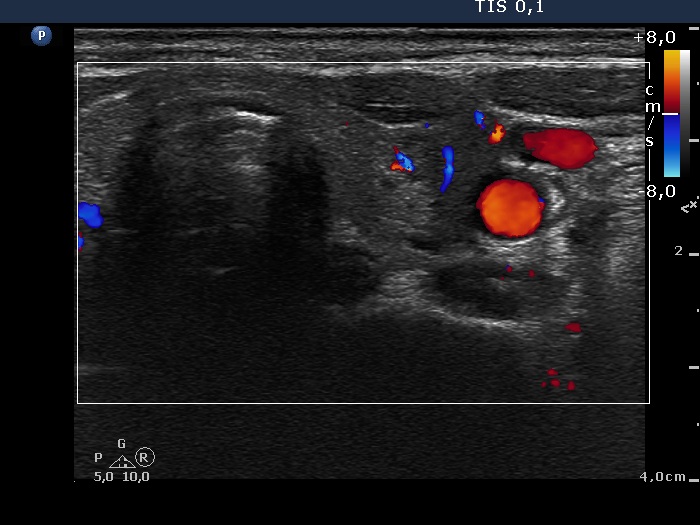

Lymph nodes - case 382 (ultrasonographic picture 6)

Left lobe, transverse scan. The lesion presents perinodular blood flow.